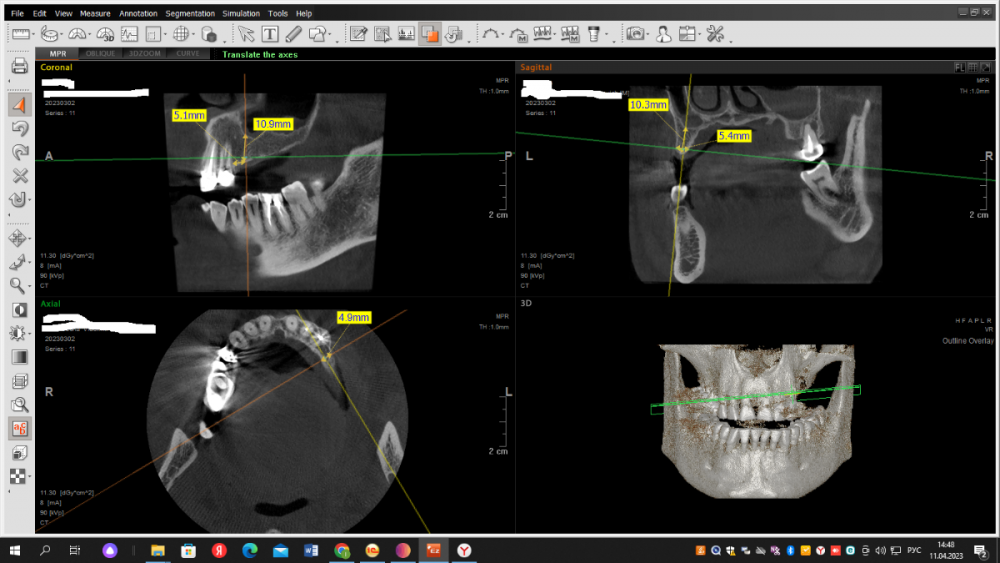

Dr T Опубликовано 13 мая, 2023 Поделиться Опубликовано 13 мая, 2023 (изменено) Уважаемые стоматологи, прокомментируйте, пожалуйста, что можно порекомендовать в данной ситуации доктору нашей клиники. Предполагался мост на имплантатах зубы 24-26, мужчина, 45 лет. Доктор выбрал 2 имплантата 4.2 по 8мм. Кость по КТ хорошая, но в ходе имплантации что-то пошло не так. В конечном итоге, один имплантат стал близко к зубу и то со второго раза и подсыпалась косточка. Можно ли оставлять как есть или слишком близко к зубу и что делать? Имплантация была 2 недели назад. На снимках первая установка и потом после попытки выпрямить 24 имплантат. Изменено 13 мая, 2023 пользователем Dr T Ссылка на комментарий

Dr T Опубликовано 14 мая, 2023 Автор Поделиться Опубликовано 14 мая, 2023 (изменено) @Irouil Насколько я понимаю, расстояние между имплантатом и зубом должно быть минимум 1,5 мм, чтобы предотвратить ишемию и резорбцию кости? Мне кажется, что легче удалить имплантат сейчас и переставить, прежде чем он интегрируется, и это предотвратит возможную потерю зуба, имплантата или того и другого. Если его оставить для наблюдения за симптомами, будет сложнее решить проблему после его интеграции, плюс гарантированные трудности с протезированием? Стоимость не проблема. Вопрос как лучше для пациента? Изменено 14 мая, 2023 пользователем Dr T Ссылка на комментарий

Irouil Опубликовано 14 мая, 2023 Поделиться Опубликовано 14 мая, 2023 @Dr T лучше для пациента сделать все правильно, а Вы говорите, что Вам кажется 4 часа назад, Dr T сказал: что легче удалить имплантат сейчас и переставить "Легче" это не "лучше", у пациента имплант уже стоит и если Вы его удалите - точно столкнёте пациента с повторной операцией, дополнительным ожиданием... Чтобы дать точный ответ нужно провести внутриротовые замеры и сопоставить данные с КТ, но ВЕРОЯТНЕЕ ВСЕГО лучше для пациента, в отсутствии симптоматики, протезировать его так, ибо условия позволяют, соблюдая современные протоколы, получить качественный результат. Лично я бы именно так и поступил. НО! Я у Вас в клинике не работаю, а что и как будет делать лечащий врач я не знаю. Более того - Вы тоже не знаете, ибо Вы не являетесь лечащим врачом пациента. Поэтому все эти обсуждения, на мой взгляд, развивать бесполезно - возможно у Вас работает первоклассный специалист, который действительно не создал себе нерешаемых проблем на следующий этап лечения и который уверен в качествах своего коллеги протезиста, способного завершить кейс в выбранном русле. Возможно и иное - доктор создал сложную ситуацию, которую ни у него, ни у его коллег по клинике способностей решить не хватит и стоит все снести и переделать пока не поздно. Выбор делать только Вам, здесь на форуме искать толковых советов бесполезно. P.S. 1.5 мм между имплантом и зубом - это крайне устаревшие данные, вроде той, что минимальная толщина альвеолярного гребня для имплантации должна быть 6.5мм. На сегодняшний день мы отталкиваемся от значений 0.8 мм для многокомпонентных имплантов. Ссылка на комментарий